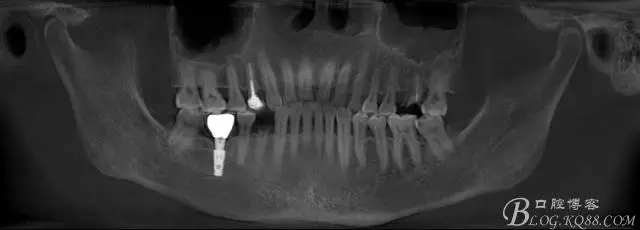

那么看下術(shù)前CBCT吧

上圖為術(shù)前CBCT情況,26號牙顯示頰根和腭根間有一比較大的區(qū)域骨頭吸收,對于即刻種植還是有難度的,植入深度需要適當(dāng)加深,那么也許使用BICON 種植體相對更加合適

上圖44號牙位做即刻種植毫無難度可言,我們要做的只是患者術(shù)后反應(yīng)更小,植入方向更好而已